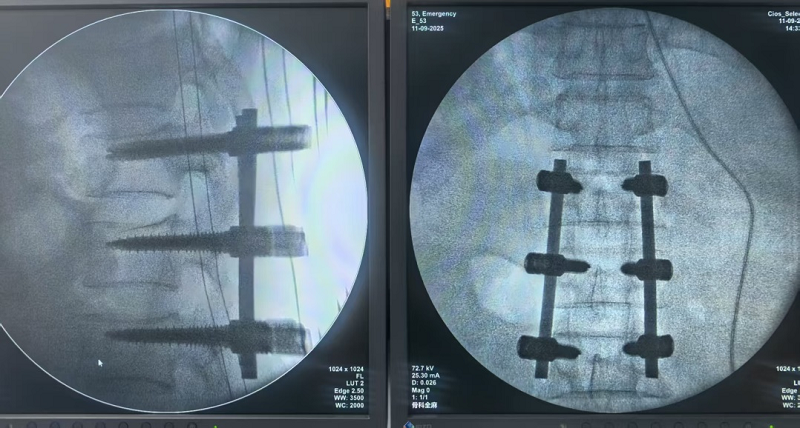

经过严谨细致的术前评估和准备,9月11日,骨科副主任医师徐勇率领团队为患者实施了“腰椎骨折切开复位内固定术”。

首例脊柱内固定术的成功开展,不仅是中心在脊柱外科领域实现“从无到有”的跨越,更是其综合医疗实力的有力印证。目前,患者术后恢复情况良好,已能在专业指导下进行早期下床活动,康复进程顺利推进。